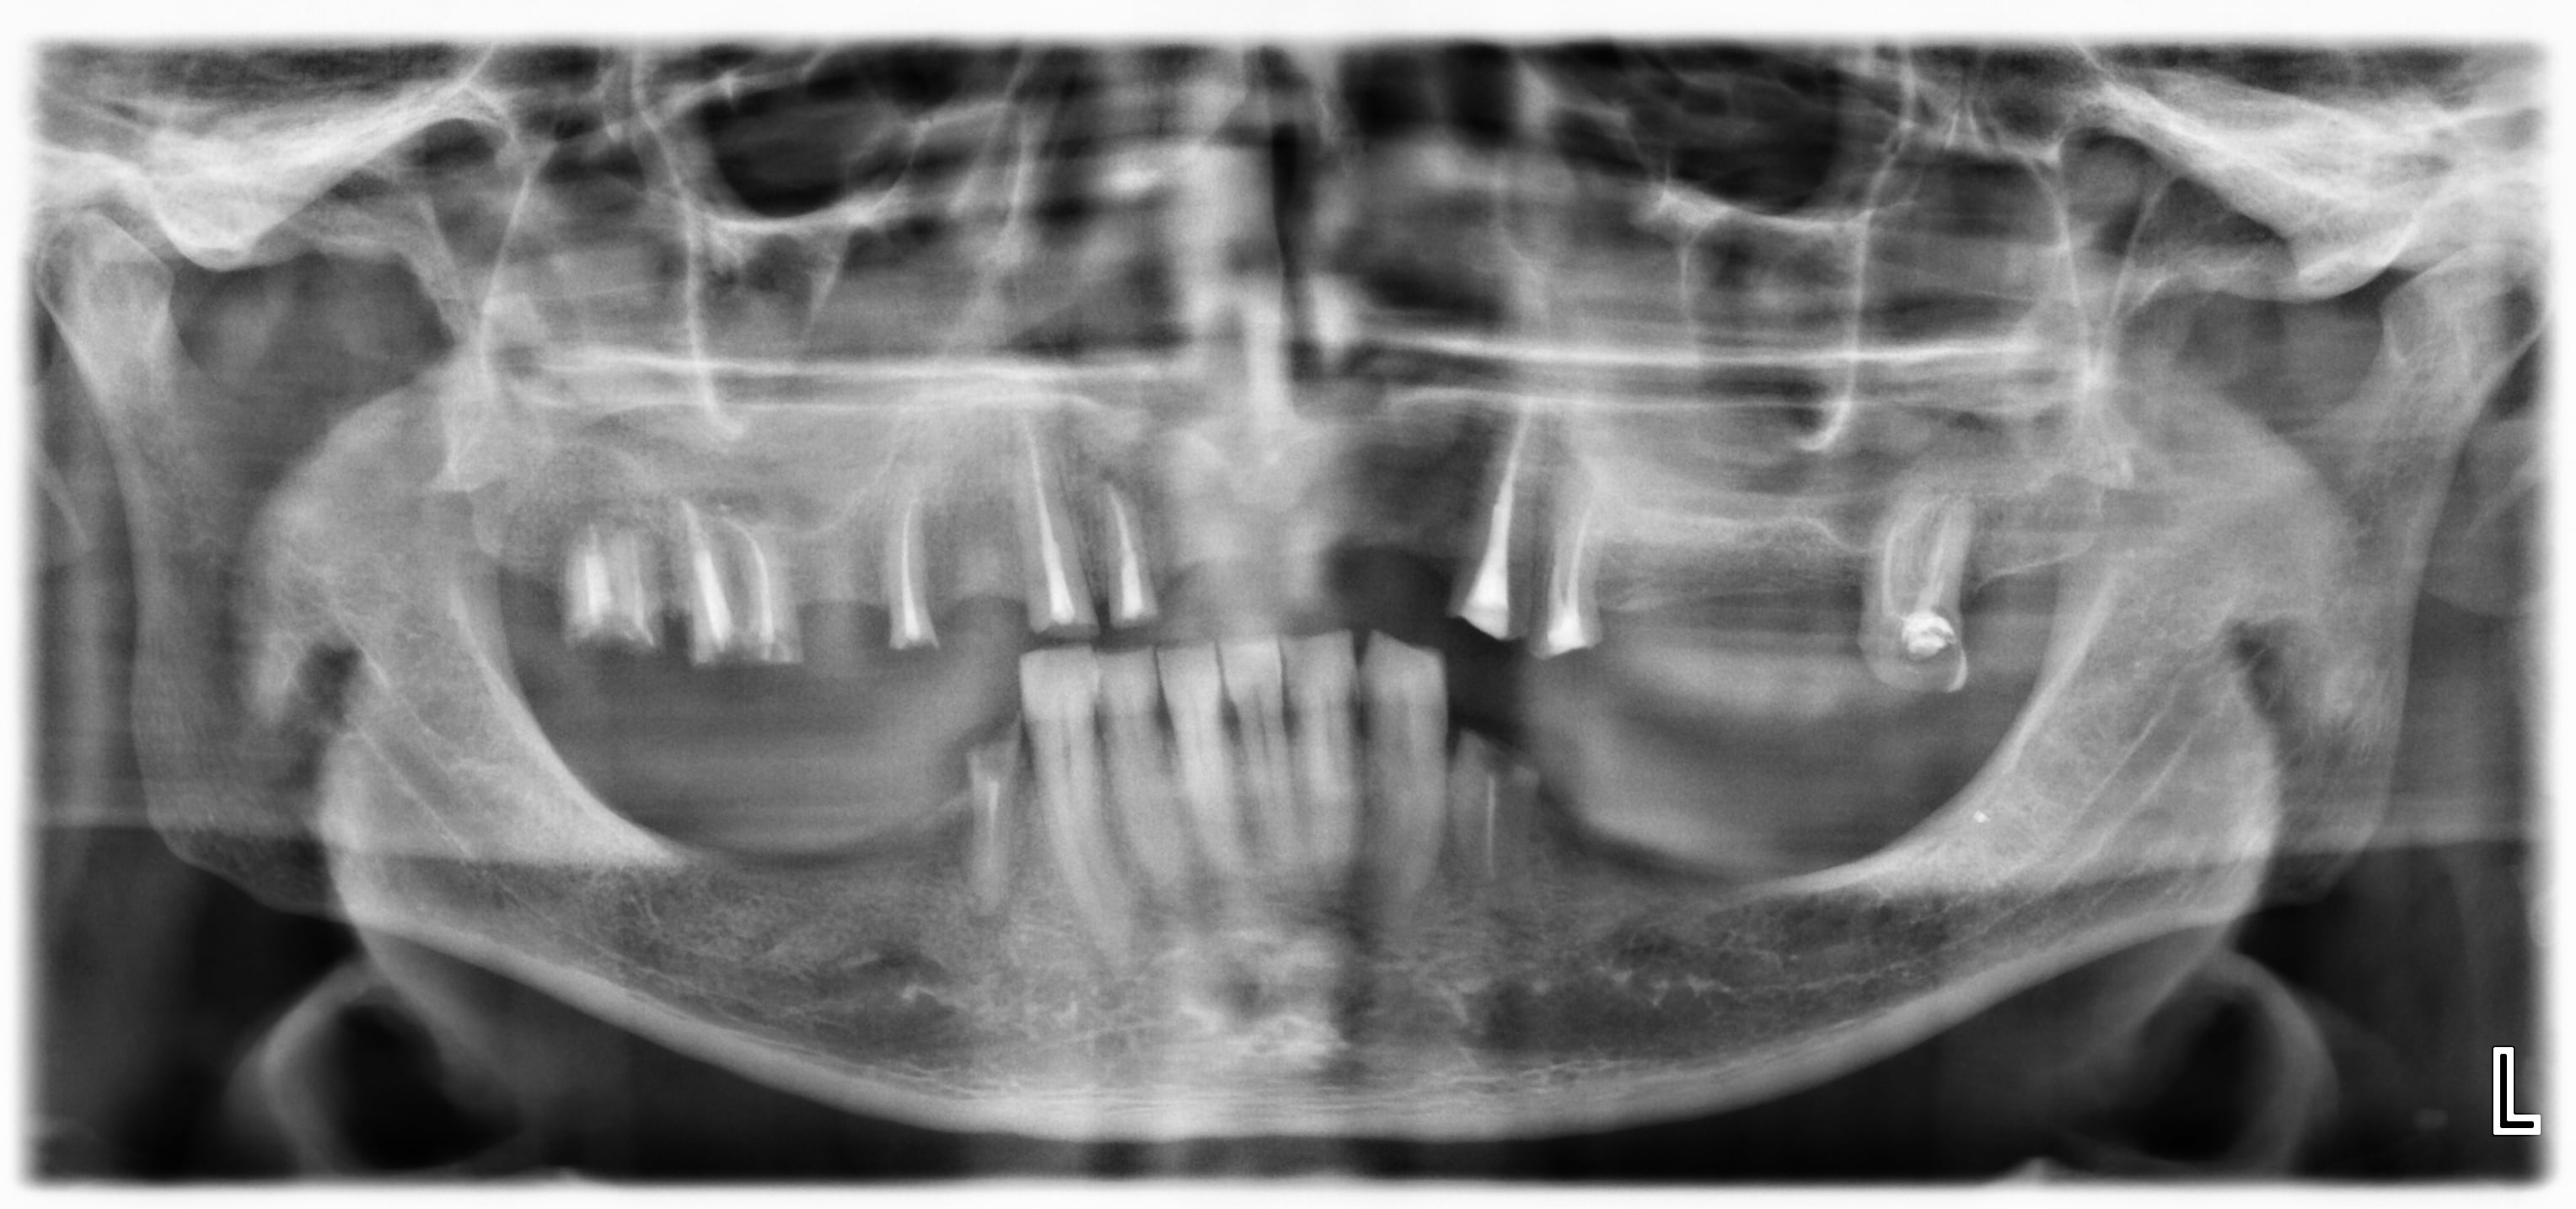

Patient 45 ans, pas d'ATCD médicaux, CMU-C suite à licenciement.

Porte actuellement un complet provisoire maxillaire au-dessus de ses racines, laissées en jachère il y a 4 ans (il n'avait pas la CMU à l'époque, et pas les moyens financiers de faire de la fixée)

Les dents résiduelles sont les vestiges de bridges déposés et d'avulsions

17, 18 et 27 récidive de carie dans le plancher pulpaire, à extraire.

Pas de lésion péri-apicales sur les autres dents (confirmé par rétro-alvéolaires, y compris sur 12)

Y'a rien sur 12, confirmé par la TIB (ça m'a aussi surpris)

Les endo étaient recouvertes d'IRM, de 15 à 24 la gutta est dure à la réouverture comme si ça datait de la veille.

Sans vouloir être rabat joie les molaires me semblent compromises dans l'optique d'une prothèse fixe de grande étendue.....

Les furcations semblent pas loin et le plancher résiduel faiblard ou vu de tes radios me paraissent peu propices à la réalisation de piliers d'appui pour des bridges durables.